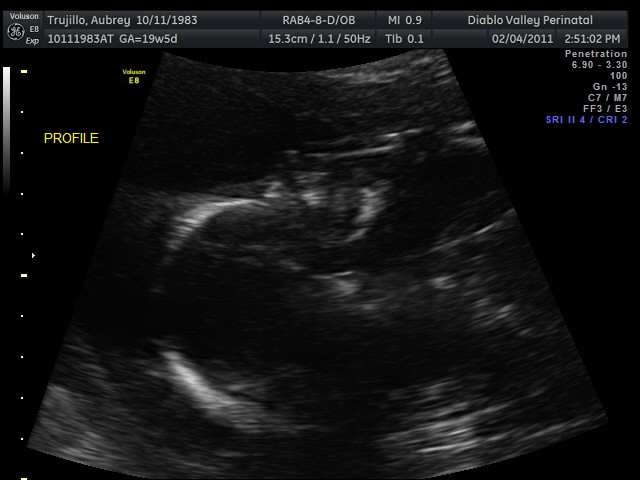

20 weeks - profile20 weeks - Profile again20 weeks - Right foot!20 weeks - sucking thumb!!!!20 weeks - hand near face20 weeks - flexing his bony arms!20 weeks - hiding from mommy and daddy!20 weeks - it's a boy!33 weeks - 3D!33 weeks - 3D!33 weeks - 3D!